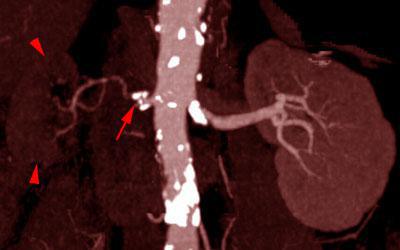

Estenosis intensa de arteria renal 2

VR MIP. Visión anterior. Riñón derecho de pequeño tamaño, apenas contrastado (puntas de flecha), secundario a estenosis ateromatosa de la arteria renal derecha (flecha)